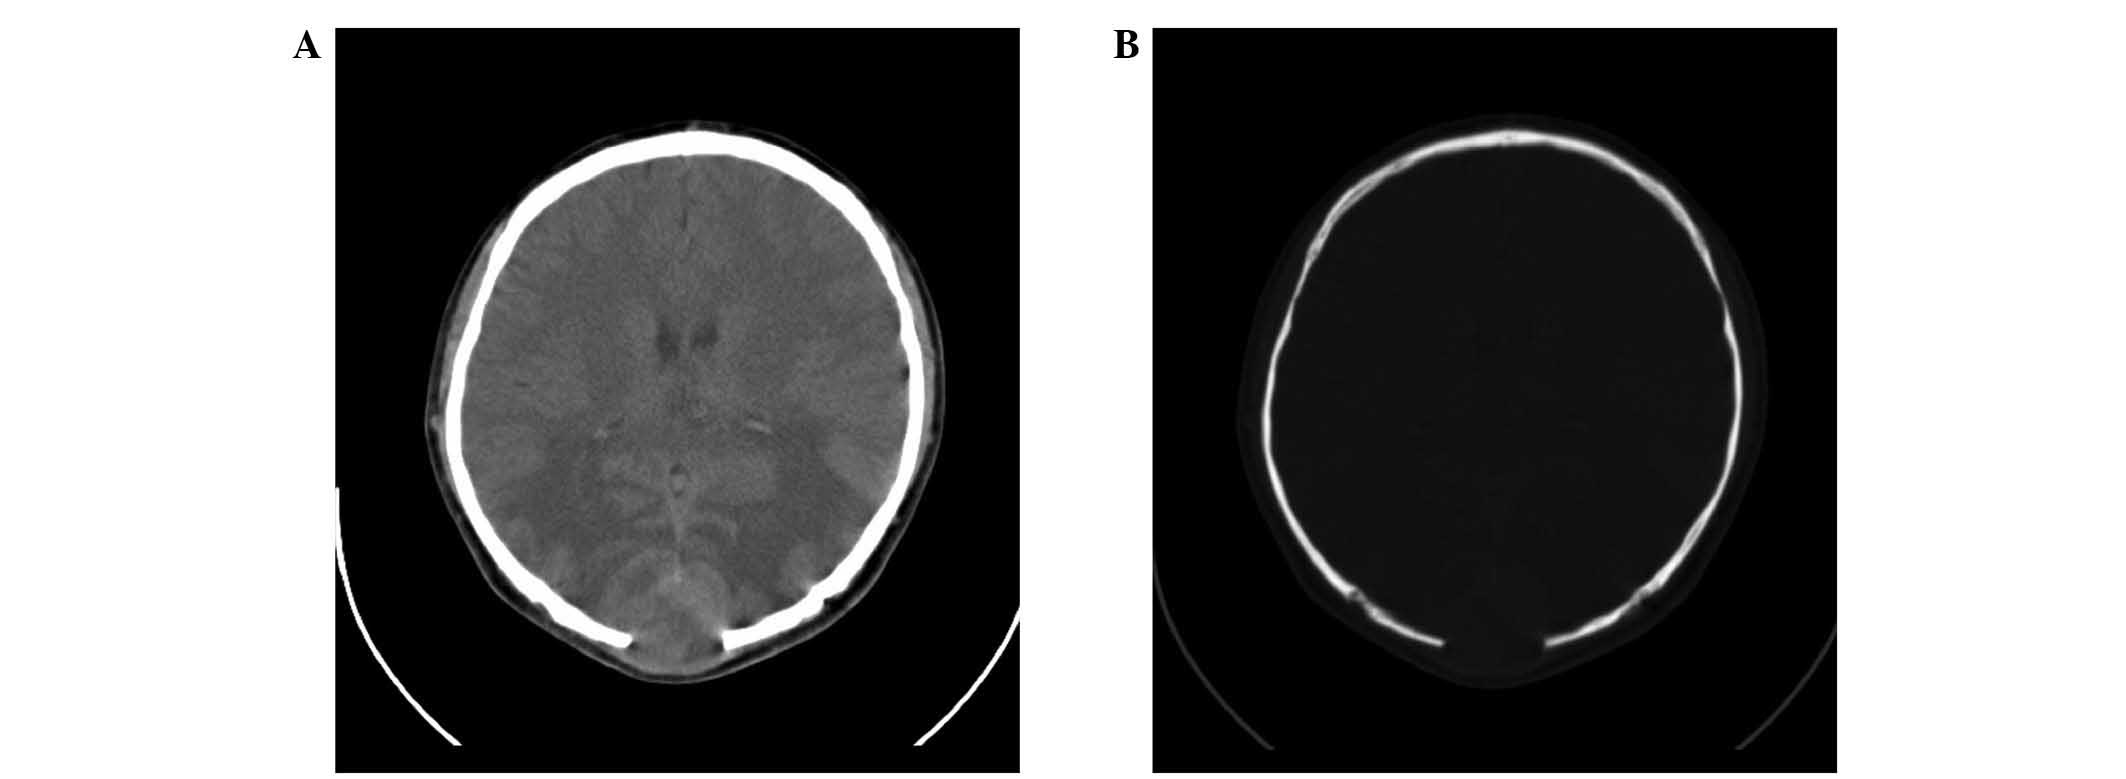

CT imaging (SOMATOM Sensation 16; Siemens Healthcare GmbH, Erlangen, Germany) demonstrated an oval-geographic, osteolytic lesion within the squamous part of the occipital bone, with a well-demarcated intracranial, calvarial and extracalvarial soft tissue mass (Fig. 1). MRI (Signa HDxt 1.5T; GE Healthcare, Fairfield, CT, USA) revealed a focal, 5.0×4.5×3.5-cm mass with bilateral occipital lobe invasion. The mass exhibited hypo- and iso-signal intensity on T1-weighted imaging and mixed-signal intensity on T2-weighted imaging. Gadolinium-enhanced images revealed prominent perilesional enhancement, particularly in the region adjacent to the brain. Irregular hypointense areas within the mass were visible on T2-weighted imaging, without obvious enhancement (Fig. 2). MR venography (Sonata 1.5T; Siemens Healthcare GmbH) was also applied to evaluate the cerebral vein system. MR venography and MRI indicated that the superior sagittal sinus and torcular herophili had been invaded, and associated vasogenic cerebral edema due to mass effect was noted (Figs. 2 and 3).

Figure 1.

Axial computed tomography imaging of the brain. (A) Soft tissue window images demonstrated a well-demarcated, intracranial, calvarial and extracalvarial soft tissue mass. (B) Bone window images revealed an oval-geographic osteolytic lesion arising from the occipital bone. No bony sclerosis or periosteal reaction was observed.

Radiological findings, although scarce in the literature, were distinctive in the current case. The imaging findings demonstrated a well-defined, heterogeneous, intracranial, calvarial and extracalvarial mass with bone destruction. The osteolytic lesion presented sharp borders, a lack of bony sclerosis and a paucity of periosteal reaction. The adjacent brain and venous sinus were invaded. These appearances may reflect the malignant biological behavior of the tumor. On T2-weighted MRI without enhancement, irregular areas of low signal intensity were visible, a characteristic which may be observed in areas of decreased cellularity and dense fibrous tissue or collagen deposition (10). High signal intensity on T2-weighted images without enhancement is considered to indicate necrosis (11,12). Intense perilesional enhancement of the tumor-adjacent brain region on gadolinium-enhanced MR images may be associated with histopathological changes, which include cellular and vascular proliferation, peritumoral desmoplastic reaction and inflammatory cell infiltration. This enhancement pattern may also be indicative of malignant tumors (13). Therefore, in the current case, imaging findings successfully suggested a tumor of high malignancy containing necrosis and fibrous tissue.